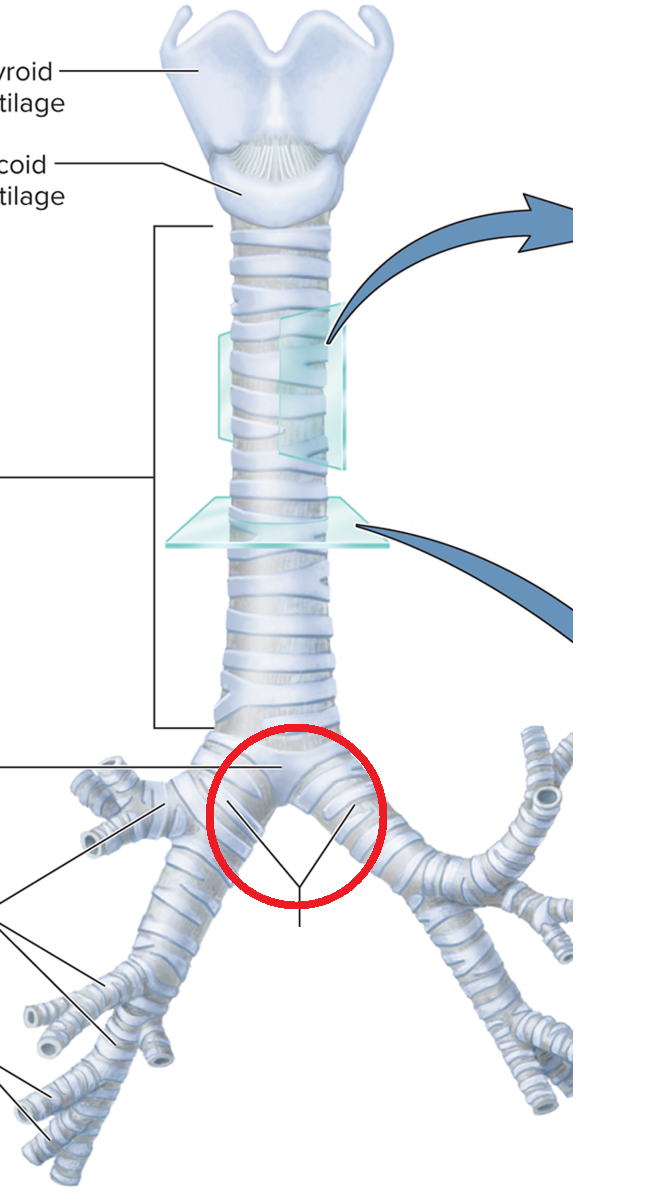

Trachea and Bronchial Tree

Carina T

Tracheal bifurcation T

Main bronchi BT

Lobar bronchi BT

Segmental bronchi BT

Bronchiole BT

Terminal bronchiole BT